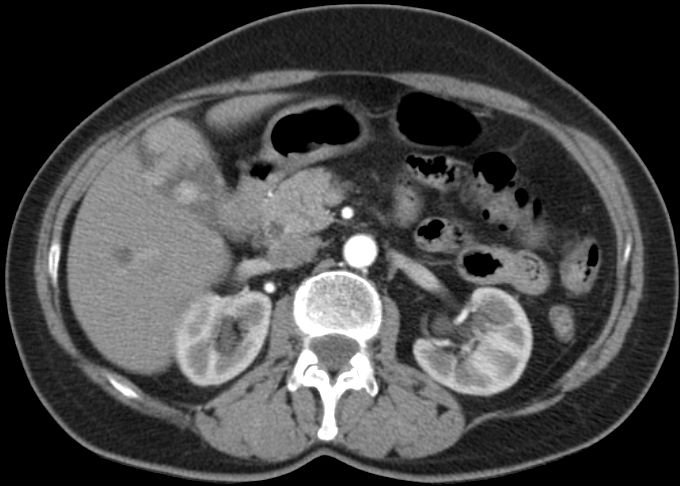

86-jähriger Mann, bei dem vor 9 Monaten eine Cholezystektomie wegen gedeckt perforierter Cholezystitis vorgenommen wurde. Jetzt Verdacht auf Leberabszess. Die laparoskopische Biopsie ergab ein Adenokarzinom. Die Nachbefundung der Gallenblase erbrachte immunhistochemisch den Nachweis eines Gallenblasenkarzinoms. | ||